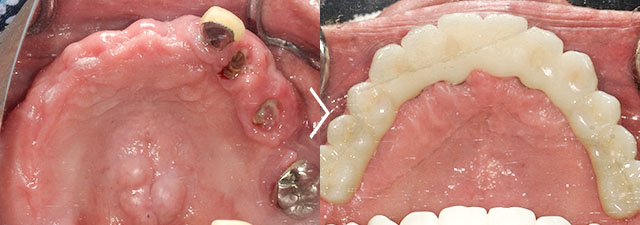

この患者様は上顎をすでにオールオン6で治療済みで、今回は下顎をオールオン6で治療しました。

オールオン6 セラミックタイプ ¥3,100,000(税抜)